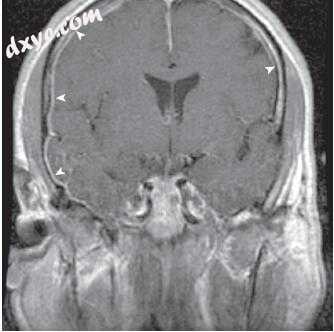

图-14. 影像学表现在急性化脓性迷路炎。 A,颞骨计算机断层扫描(CT)显示慢性乳突炎伴乳突、外耳道和中耳混浊。 注意侵蚀和前庭介入(箭头)。 B,冠状颞骨CT扫描显示内耳道底部的侵蚀和累及(箭头)。 C,轴位对比增强T1加权磁共振成像(MRI)显示中耳,前庭和内听道增强(箭头)。 D,冠状对比增强T1加权MRI显示增强颞叶硬脑膜(黑色箭头)和内听道(白色箭头)。

图-15. A,冠状颞骨计算机断层扫描显示颞骨脑膨出(星号)通过盖缺损(箭头)。 B,冠状位T2加权磁共振成像显示脑膨出(箭头)。